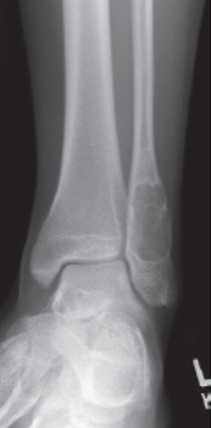

16

Q

Qual diagnóstico?

A

Lesão litica do calcâneo, borda bem delimitada

dx: COS